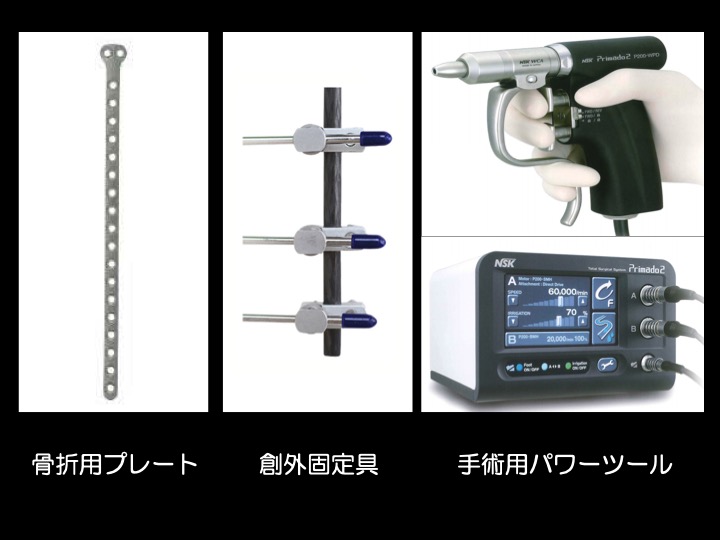

【インプラント、創外固定など】

・骨折による骨のズレが大きい場合や、ギプス固定ができない箇所の骨折などが適応になります。

・骨折の部位、動物の大きさや手術用途にあわせて選択できるよう、様々な種類のものが作られています。